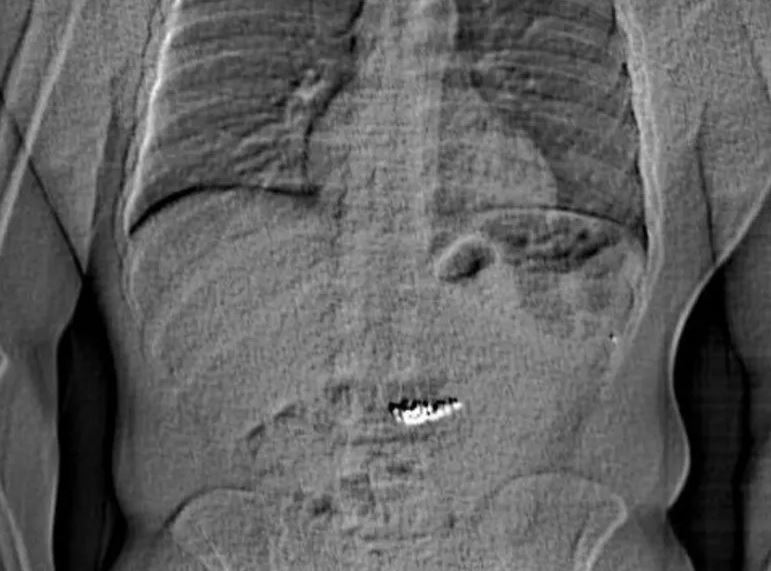

Η ακτινογραφία που, μάλλον, έδειξε τα πειστήρια

Η αστυνομία έδωσε αργότερα στη δημοσιότητα μια ακτινογραφία που φαινόταν να δείχνει την κοιλιά ενός ατόμου με ένα ξένο αντικείμενο στο εσωτερικό της.

Φωτογραφία: Orlando Police